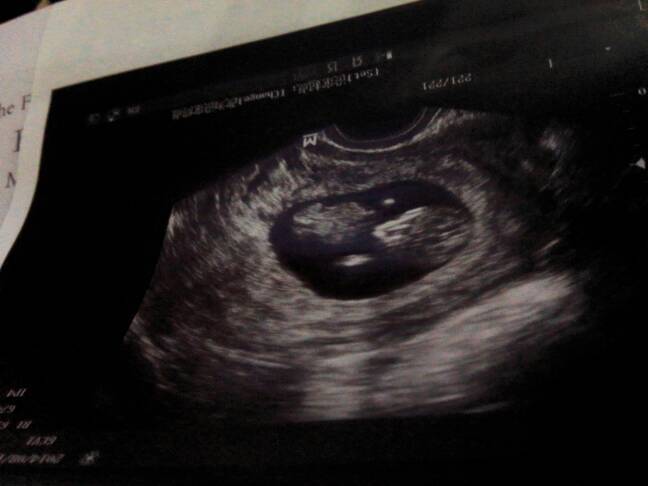

帮我看看我七十天做的B型是男孩还是女孩 帮我看看我七十天做的B型是男孩还是女孩 点击展开 无所谓的事 2014-08-30 20:25 为您推荐: 其他回答 这个是看不出来的, 婷,琳麻麻 2014-08-31 09:46 这个看不出来 世越妈 2014-08-31 00:20 图像怎么能来的出来 ╰つSay丶No 2014-08-30 20:54 不懂,再等等去做B超查的准 贤宝宝 2014-08-30 20:27 你好,谢谢咨询,根据你的彩超单子是看不出男女的,因为怀孕时间太短,不会看出来的。 圣手仁心windy 2014-08-30 20:26 加载更多 相关问题 我怀孕27多三天了,宝妈们帮我看看肚肚像生男孩还是女孩 我做了酒精试验男孩,女孩,谁帮我看看啊? 40多天胎囊大小2 4x1 3请帮我看看男孩女孩